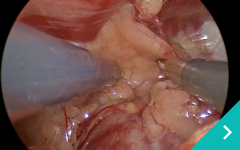

ミニマム創内視鏡下手術は腹腔鏡だけでは対処ができないような手術の際に、お腹にラッププロテクターという器具を設置して行う腹腔鏡と開腹手術を組み合わせた手術です。